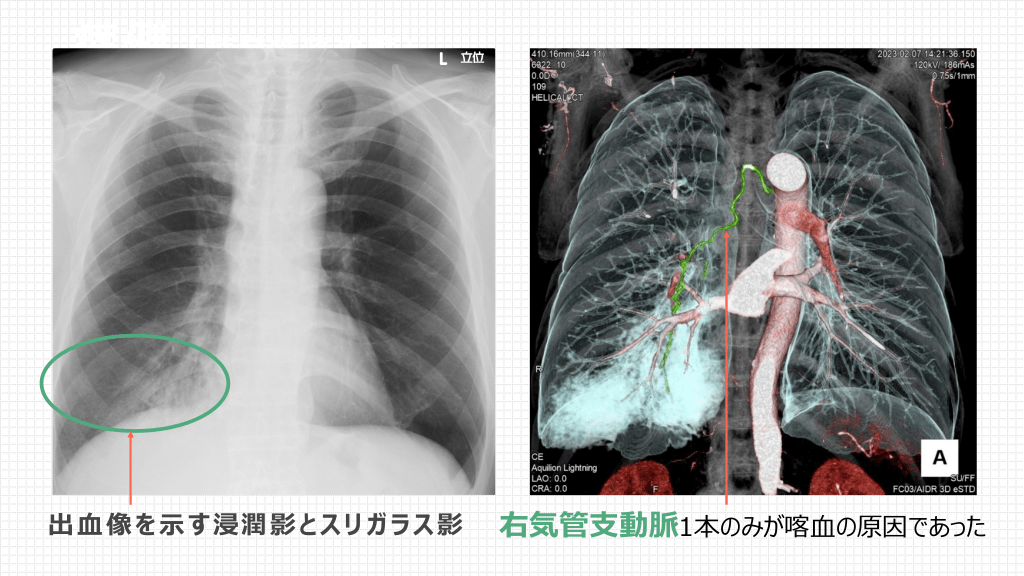

症例 ( 特 発 性 喀 ⾎ 症 ) 出⾎像を⽰す浸潤影とスリガラス影 右気管⽀動脈1本のみが喀⾎の原因であった

出症例 ⾎ の C( T画 特像 発性喀⾎症) 出⾎像はスリガラスを伴う浸潤影またはスリガラス影のみ。 気管⽀内に凝⾎塊が⾒えることもある。 これらの陰影がその後完全消失することも出⾎像である傍証となる。